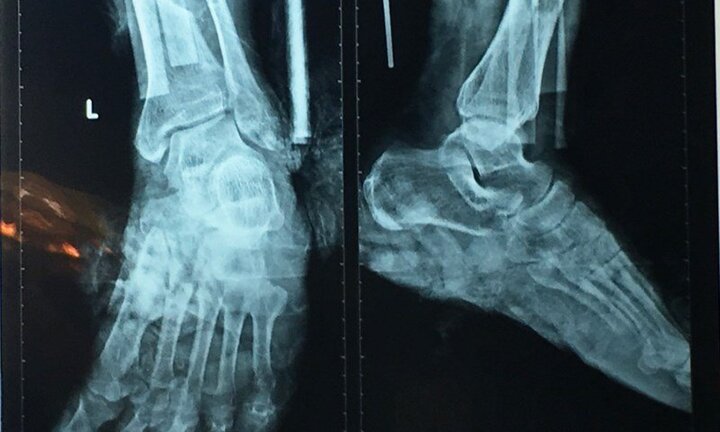

“Sau hai ngày phẫu thuật, chân trái gần đứt lìa của ông T.V.T (69 tuổi, ở Đồng Nai) đã hồng ấm, có hướng cải thiện, tuy nhiên, ông T. cần được tiếp tục theo dõi thêm 10 ngày nữa”.